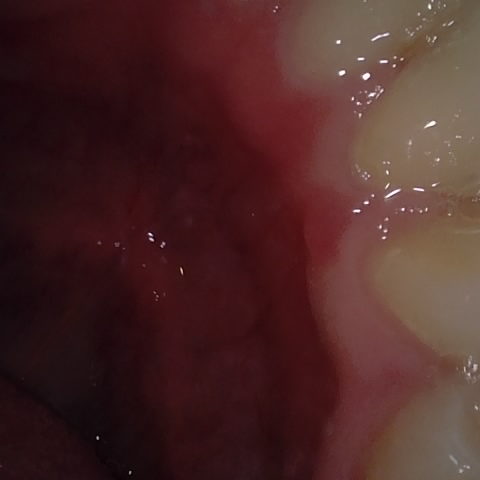

Incorrect Quality Level

The reference annotation for this image is

None

.

Please select the correct quality level.

Annotated as "Bad"